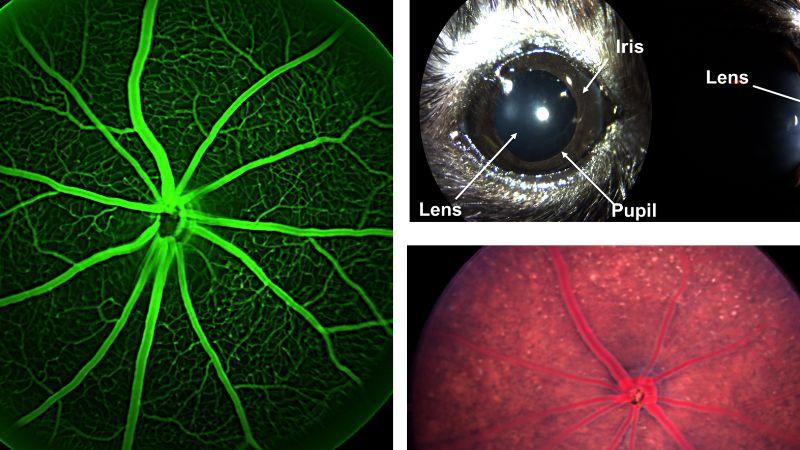

PCP Direct & Indirect Ophthalmic Exam | PCI MRI-rsfMRI, Isotropic (imaging acquisition only) |

PCP Electroretinography | PCI Ultrasonography |

PCP Fundus Imaging/Fluorescence Angiography | |

PCP Gross Morphology Photography |